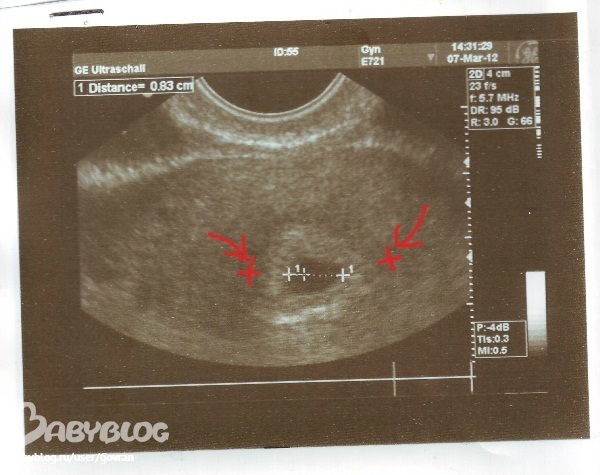

Вот судя по этому фото мерили по внутренней стороне

А вот где красными крестиками - это наружняя сторона

вот это черное пятно и есть эндометрий, в котором находится малыш... на моих снимках его еще не видно.. вот если мерить четко по краям черного пятна - то это внутренняя сторона эндометрия, а по её краям есть как светлая оболочка...(где я поставила красные крестики).... так вот её края это наружняя сторона... и вот по каким мерить правильно не понятно....